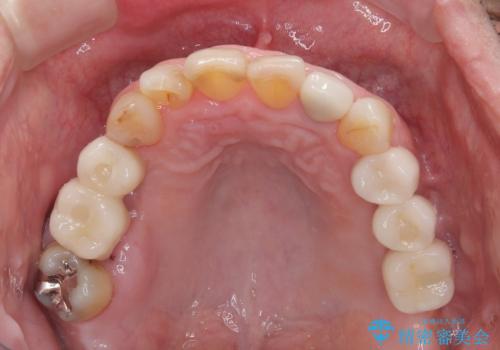

欠損の多い奥歯 インプラントによる補綴治療

右下の銀歯も気になるとのことで、インプラント治療と並行してオールセラミックによるブリッジ補綴治療も行うこととしました。

地元に戻られる前に無事に治療を終えることができました。

今後は東京出張のタイミングでメインテナンスに通院していただきながら、インプラントの状態をチェックしていくことになります。